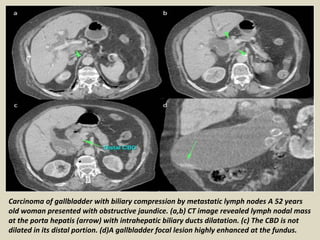

Carcinoma of gallbladder with biliary compression by metastatic lymph nodes A 52 years

old woman presented with obstructive jaundice. (a,b) CT image revealed lymph nodal mass

at the porta hepatis (arrow) with intrahepatic biliary ducts dilatation. (c) The CBD is not

dilated in its distal portion. (d)A gallbladder focal lesion highly enhanced at the fundus.

Carcinoma of gallbladderwith biliary compression by metastatic lymph nodes A 52 years old woman presented with obstructive jaundice. (a,b) CT image revealed lymph nodal mass at the porta hepatis (arrow) with intrahepatic biliary ducts dilatation. (c) The CBD is not dilated in its distal portion. (d)A gallbladder focal lesion highly enhanced at the fundus.